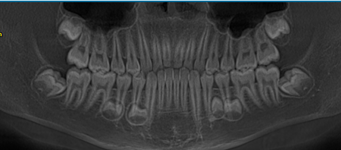

图1 全景片发现下颌骨有四个埋伏多生牙,左右各有两个